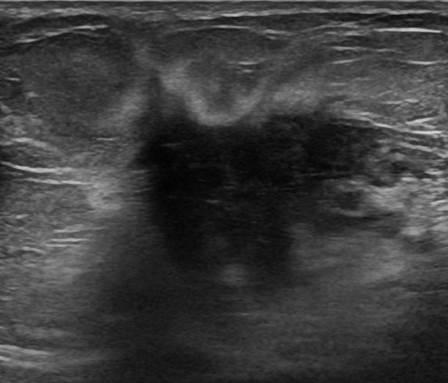

Ung thư vú

Ung thư vú - Ảnh 4

» Thông tin: Nữ giới – 58 tuổi.

» Lâm sàng: Khối tuyến vú.